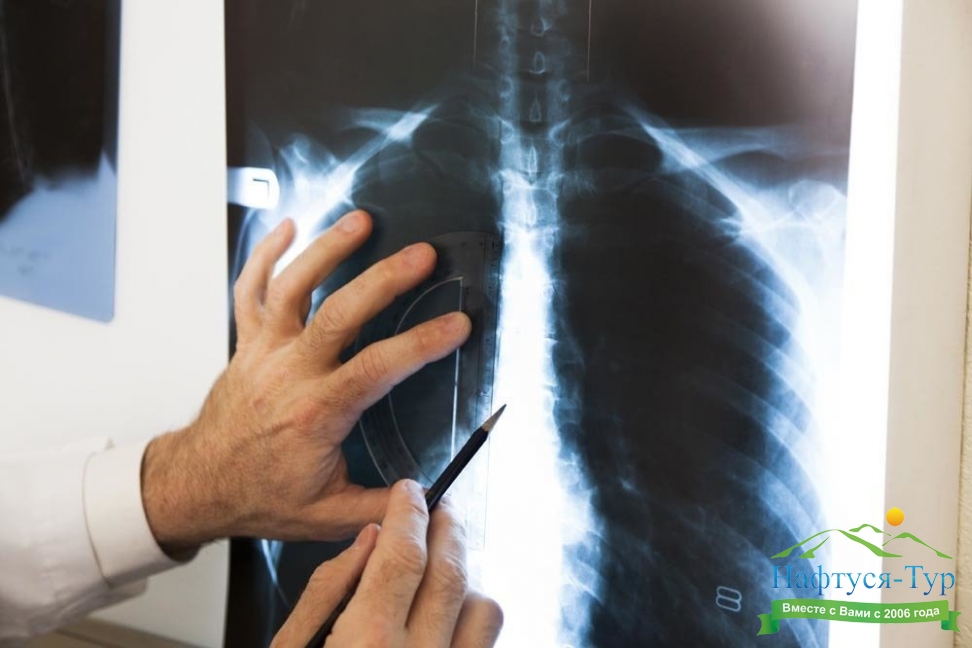

Рентген – упрощенное название неинвазивных диагностических методов, официально называемых рентгенография, рентгенологическое исследование. За счет использования рентгеновских лучей, которые проходят через тело человека, медики могут получить картину внутренних тканей и органов, определить имеющиеся патологии. В зависимости от назначений диагноста рентгенологическое исследование может проводиться в различных формах – обзорное, флюорография, ангиография, урография и так далее. Результаты исследований позволяют выявлять патологии костей, суставов, полых органов, отложения солей, скопления газов и жидкостей.Кабинет рентгенографии сегодня имеется практически в каждом санатории нашей страны. При этом многие здравницы располагают самыми современными рентгеновскими установками, управляемыми компьютером. За счет обработки данных в памяти компьютера и представления изображений в цифровой форме достигается более высокое качество диагностики, что в свою очередь позволяет проводить более эффективное лечение.